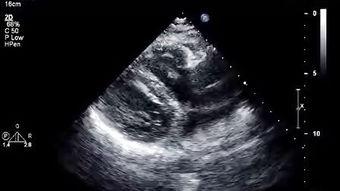

心脏彩超,顾名思义,就是利用超声波技术来观察心脏的结构和功能。它能够清晰地显示心脏的各个部位,包括心房、心室、瓣膜等,还能观察到心脏的跳动和血流情况。对于心脏疾病的诊断和治疗来说,心脏彩超就像是一把“秘密武器”,能够帮助医生们更好地了解患者的病情。

2. 实际操作演示:通过实际操作演示,你可以看到医生是如何操作心脏彩超仪器的,以及如何解读图像。